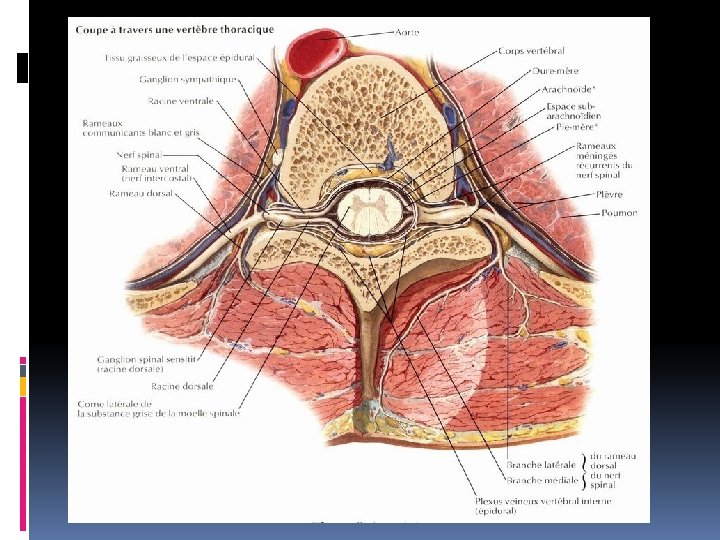

II. RAPPELS ANATOMIQUES